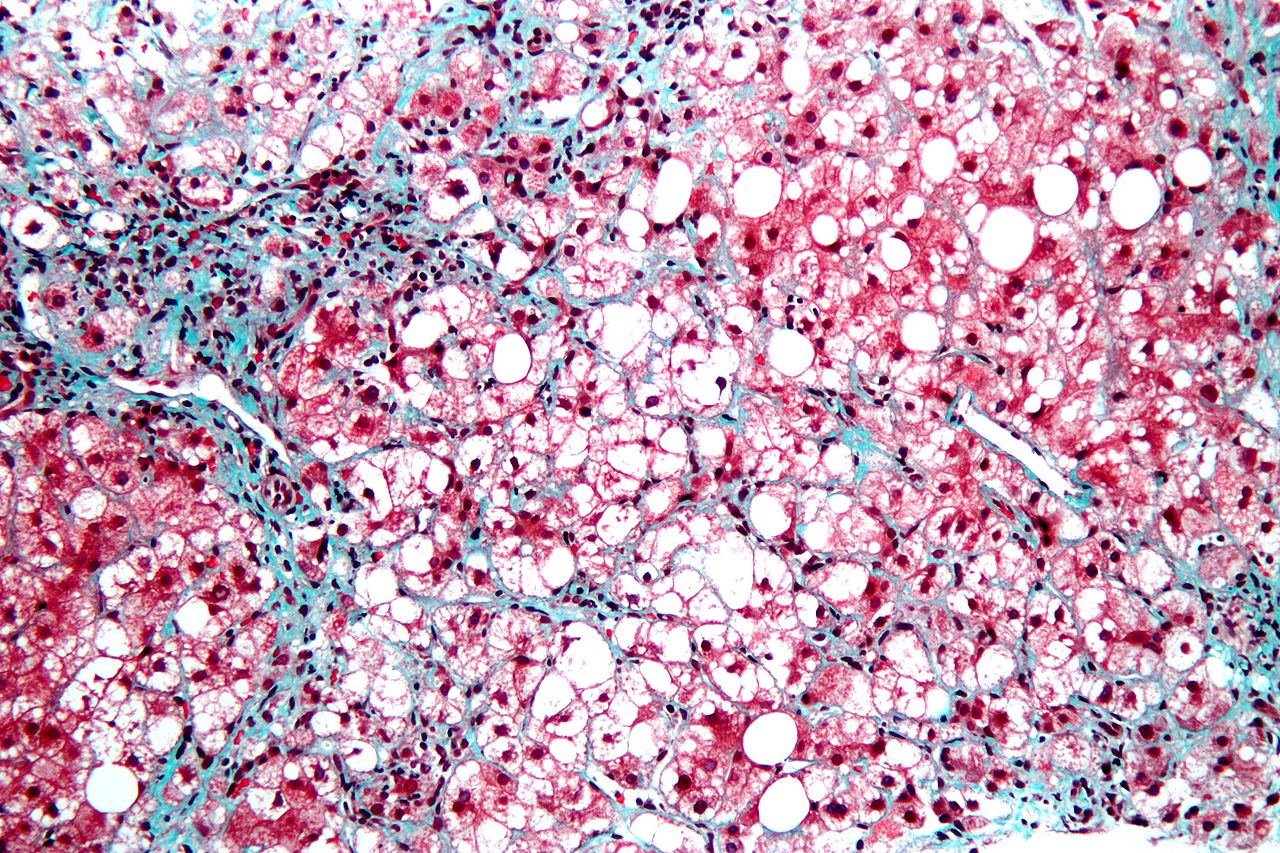

Nonalcoholic steatohepatitis (NASH) is a disorder involving fat buildup and inflammation in the liver. It is related to but more severe than non-alcoholic fatty liver disease (NAFLD), which affects an estimated 25% of US adults. In addition to the steatosis (fat buildup within cells) and inflammation, which are hallmarks of the disorder, NASH can also involve damage to hepatocytes and progressive liver fibrosis, which can eventually lead to cirrhosis. Risk factors include obesity, diabetes or prediabetes, age over 40 years, and high blood triglycerides, among others.